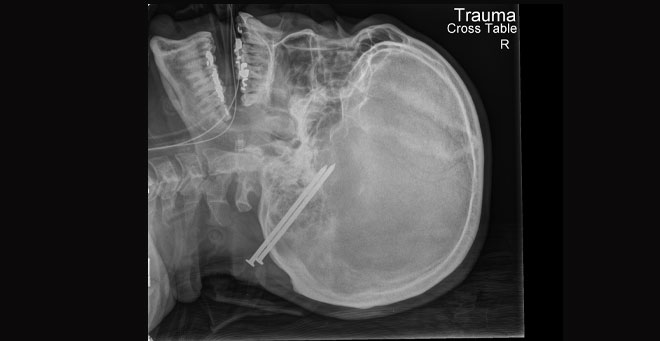

UMass Chan researchers help develop novel tool to predict survival after penetrating brain injury

A new tool developed by researchers at UMass Medical School, the R Adams Cowley Shock Trauma Center at the University of Maryland and Yale School of Medicine may help predict a person’s chance of survival after a gunshot wound or other penetrating brain injury.

“Gunshot wounds are the number one cause of penetrating traumatic brain injuries,” said lead author Susanne Muehlschlegel, MD, MPH, associate professor of neurology. “Much of our knowledge about surviving such injuries comes from the battlefield, not from shootings among civilians. The first thing family members want to know when a loved one has a brain injury is whether they will survive. Being better able to determine the average person’s chance of survival could help doctors and families make important decisions about medical treatments.”